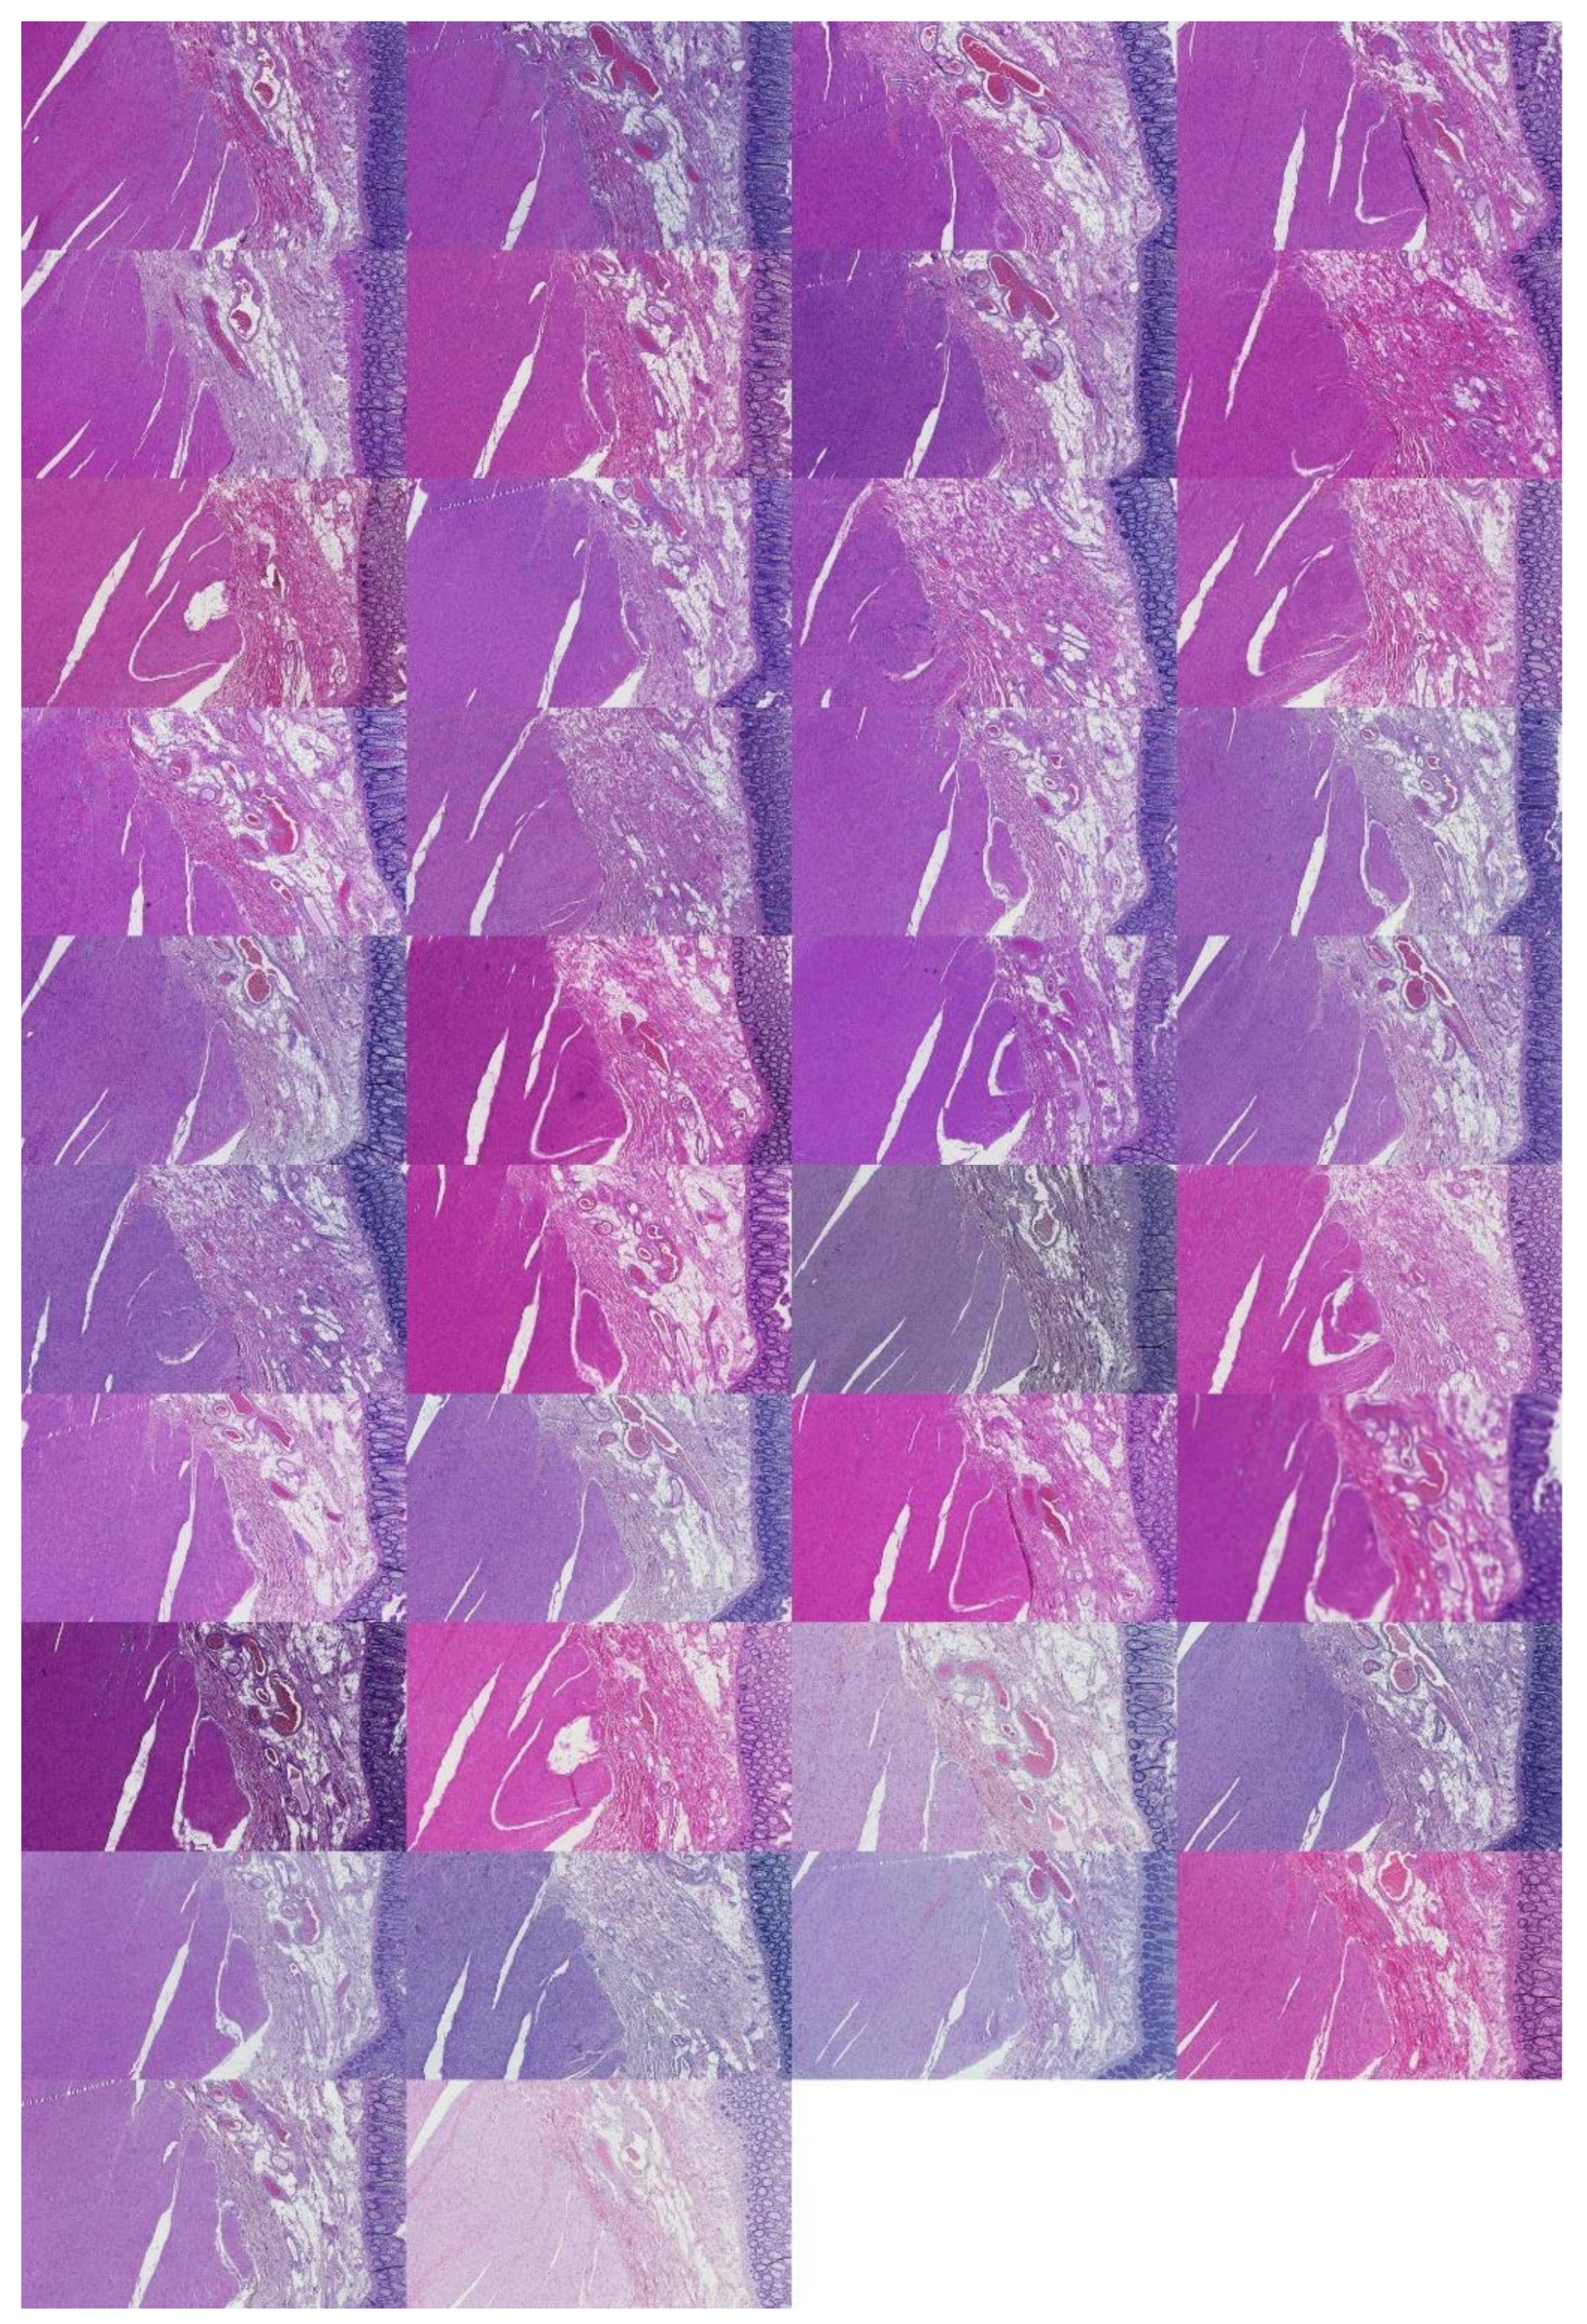

Figure A5.

Kidney examples visualized by descending silhouette score within the first cluster found (C1). Silhouette values descend in the left direction from the left-most example in the first row.

Figure A6.

Kidney examples visualized by descending silhouette score within the second cluster found (C2). Silhouette values descend in the left direction from the left-most example in the first row.